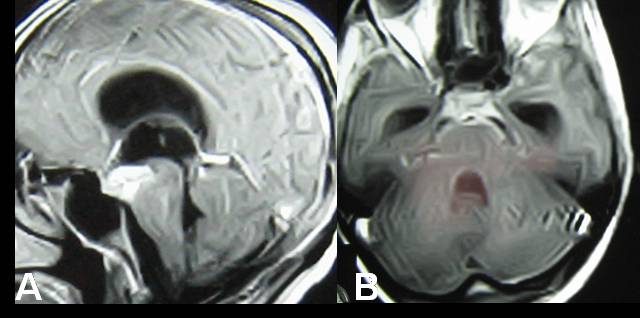

Intracranial tuberculomas are rather common lesions in developing world.Tuberculomas are usually located in cerebellum, basal ganglia and cerebral hemispheres, particularly in frontoparietal region.Less common sites include the corpus callosum, quadrigeminal plate,the cerebellopontine angle, the retro-orbital region, the anterior optic pathway and the supraseller region.The central nervous system (CNS) involvement comprises approximately 1015% of all tuberculous infections. Brain tuberculosis is usually parenchymal. Intraventricular tuberculosis is very rare and only little number of cases has been reported. Intraventricular tubercular abscess is further rarer. Here we report a case of third ventricular tubercular abscess with triventriculomegaly that was managed by ventriculoscopic drainage and third ventriculostomy though preoperative diagnosis & surgical planning was different.